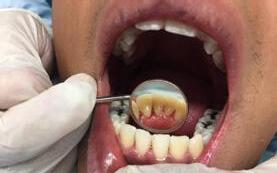

Se presenta un paciente de 29 años de edad. Al interrogatorio clínico refiere no tener alteraciones sistémicas y que actualmente no está tomando ningun medicamento, acude a la consulta odontológica para que le realisen una limpieza. En la revision clínica se observa la presencia de bioplaca y con sarro en los organos dentarios (OD) del 32 y 42 por la superficie vestibular. Por lo que se indica una profilaxis, se procedió de la siguiente manera, tinción de la bioplaca (Figura 1), realizándose el levenatmiento del índice epidemiológico IHOS. Se obtuvo el promedio de

Figura 1. Frente de inicio.

Figura 2. Vista lingual inferior dientes con sarro.

la bioplaca, el cual fue bajo según el IHOS 0.6 y el sarro se localizó en los OD Inferiores 32 y 42 por las superficies vestibular y lingual.

En la Figura 2 se ven los organos dentarios del 32 al 42 con sarro en la superficie lingual abarcando menos del tercio medio.

Se llevó a cabo la profilaxis para retirar el sarro (Figura 3), una vez eliminado se procedió al cepillado de todas las superficies dentarias.